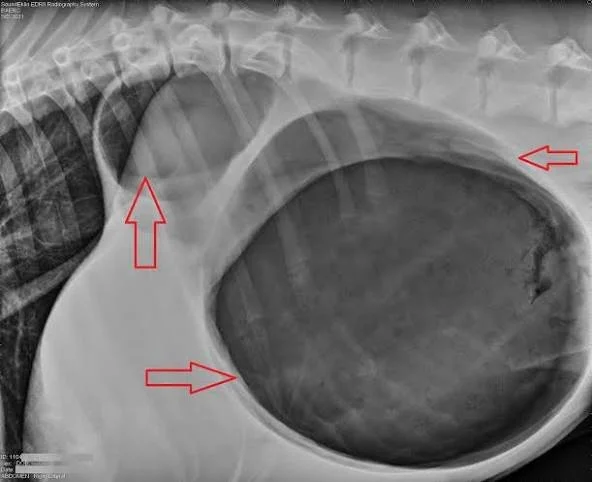

Bloat in Dogs (GDV): Symptoms, Causes, and Treatment

Bloat in dogs (GDV) is a life-threatening emergency where the stomach fills with gas and twists. Learn the symptoms, causes, and when to seek veterinary care.